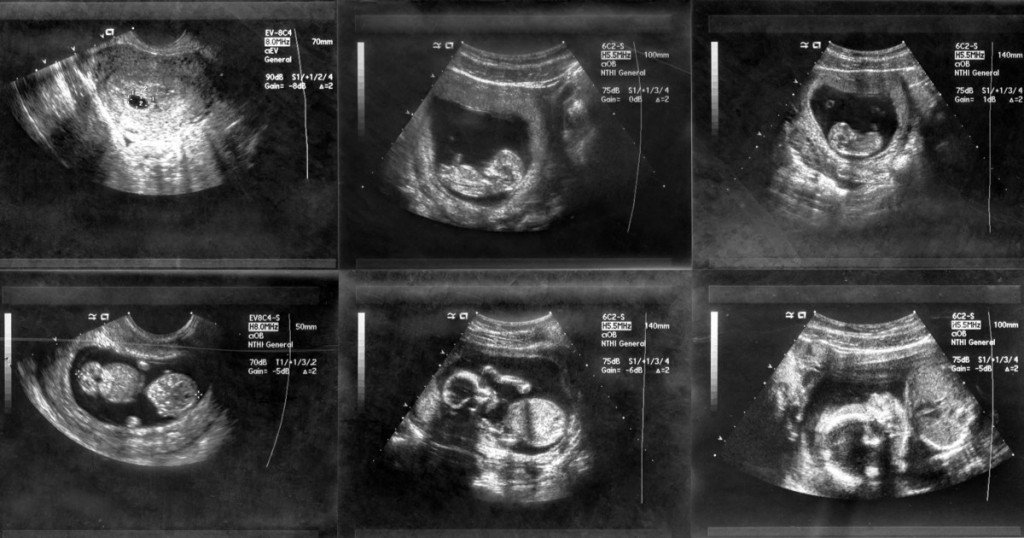

Основное отличие трёхмерного УЗИ от двухмерного — это изображение, которое мы получаем при исследовании. При двухмерном УЗИ картинка получается плоская, двухмерная, чёрно-белая, которую достаточно сложно разобрать непрофессионалу.

При двухмерном УЗИ изображение получается чёрно-белое, и его достаточно сложно понять человеку, не связанному с медициной